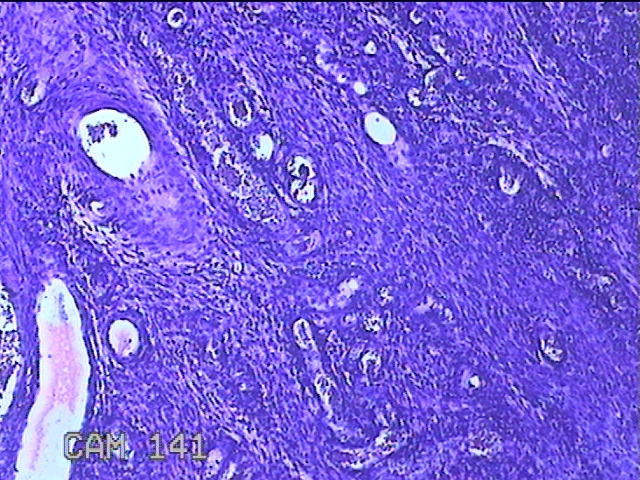

宫颈赘生物

性别

女

年龄

49岁

临床诊断

人乳头瘤病毒感染

一般病史

宫颈HPV阳性TCTLSLL

标本名称

大体所见

灰白粉红色肿物1.2x0.8x0.2cm两个,表面光滑。

图3